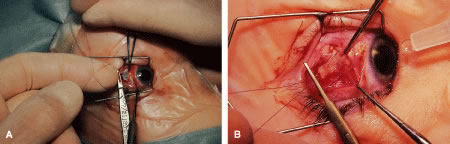

RESECTION PROCEDURE: LIMBAL APPROACH

Incision is made into the conjunctiva at the limbus (Fig. 64).

|

The assistant elevates the conjunctiva while the surgeon uses a Stevens' hook to elevate the rectus muscle (Fig. 65). A Jameson muscle hook is passed under the muscle tendon in a plane that is tangential to the scleral surface, about 3 mm behind the tented rectus muscle insertion. Figure 66 shows the rectus muscle on the Jameson hook.

|

The surgeon cuts the intermuscular septa free from the muscle capsule (Fig. 67). A Castroviejo caliper is used to measure the amount of tendon that will be resected (Fig. 68). A Jameson resection clamp is placed on the muscle at the point of anticipated resection. Measurement is made from the portion of tendon that is on the posterior edge of the Jameson hook to the resection clamp. Exposure is facilitated with a Desmarres retractor.

|

|

The muscle is cut free from its insertion (Fig. 69). The surgeon holds the Jameson clamp to elevate the muscle from the globe, and, using the other hand, the surgeon cuts the muscle free from the globe. The muscle stump is cut so that it is flush with the globe.

|

The globe is stabilized with a 0.5-mm-toothed Castroviejo forceps (Figs. 70 and 71). A mattress stitch with a double-armed 6-0 synthetic absorbable suture is placed through the most inferior portion of the insertion. The second needle is passed 1 mm below the central portion of the insertion. The initial penetration of the needle is just anterior to the insertion, and a secure bite is taken of the former insertion so that the needle exits just posterior to the old insertion. The needle is then passed underneath the Jameson resection clamp through muscle tendon, and the two sutures are held with a bulldog clamp to keep them separate from the sutures that are later passed through the upper pole of the insertion. Figure 71 shows the sutures being tied. This maneuver will effectively bring the resected muscle tendon up so that it can be reinserted at the insertion. Once the muscle is tied securely, the Jameson resection clamp is released and then advanced to the cut end of the insertion (Fig. 72). Under direct visualization, a Westcott scissors is used to trim the excess muscle stump. Care is taken to leave at least 1 mm of muscle tendon in front of the two sutures that secure the muscle to the insertion. After the muscle stump has been inspected, the conjunctiva is advanced back to the limbus (Fig. 73). Two 8-0 collagen sutures are used to secure the conjunctiva at the limbus. The small open radial portion of the incision will heal without suture closure. If the surgeon “buries the knots” under the conjunctiva near the limbus, the patient will have less foreign body sensation. Figure 74 shows the eye immediately after a recess-resect procedure. The conjunctiva should be smooth at the limbus to prevent disruption of the tear layer and formation of dellen. The eye is not patched. Antibiotic drops or antibiotic-steroid drops may be used at the discretion of the surgeon.

|

|

|

|